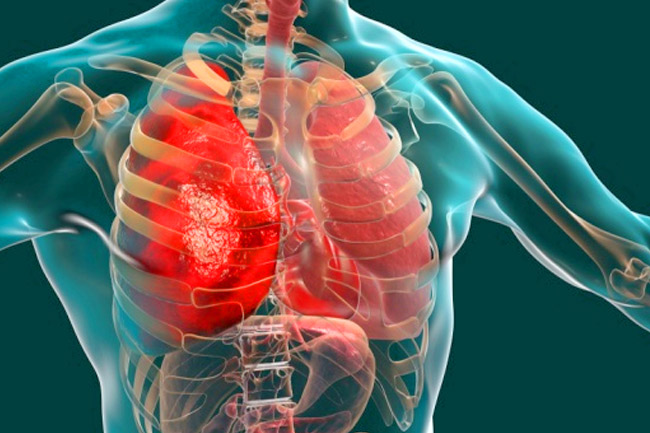

Jakarta, gatra.net– Ketua Umum Yayasan Kanker Indonesia, Prof. DR. dr. Aru Wisaksono Sudoyo, Sp.PD-KHOM, FINASIM, FACP menjelaskan, kanker paru adalah jenis kanker yang kejadiannya paling tinggi pada laki-laki di Indonesia. Karena 95% kanker paru akibat lingkungan serta gaya hidup dan kebiasaan merokok.

Lebih lanjut Prof. Aru menyampaikan, gejala pada kanker paru seringkali tidak tampak pada stadium awal. Hal ini berakibat dimana data saat ini menunjukkan bahwa 60% pasien kanker paru datang dalam stadium lanjut. Sebab seringkali kanker paru memiliki gejala yang serupa dengan penyakit umum lainnya, seperti TBC.

Menurut dia, salah satu hal yang menjadi sangat memprihatikan adalah angka kematian akibat kanker paru dalam kurun waktu kurang dari satu tahun di Indonesia terus meningkat. Hal ini merujuk data Globocan 2018, dimana angka kematian akibat kanker paru untuk wilayah Asia secara keseluruhan justru mengalami penurunan sebanyak 3%.

Adapun 85% sampai 95% kanker paru adalah dari jenis “kanker paru-paru bukan sel kecil” atau disebut juga dengan kanker sel gandum. Dimana 10% hingga 15% dari seluruh jenis kanker paru ini dengan sifat cenderung menyebar dengan cepat.

Khusus untuk kondisi kanker paru di tanah air, Data GLOBOCAN 2020 menunjukkan bahwa kanker paru merupakan penyebab kematian kanker tertinggi di Indonesia dengan 84 orang meninggal dan 95 kasus baru terdiagnosa setiap hari nya.